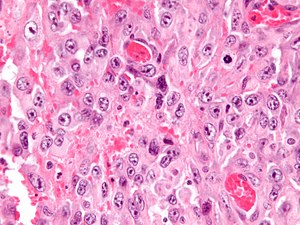

| Micrograph of an epithelioid sarcoma. H&E stain. | |

Histologically, epithelioid sarcoma forms nodules with central necrosis surrounded by bland, polygonal cells with eosinophilic cytoplasm and peripheral spindling.[3] Epithelioid sarcomas typically express vimentin, cytokeratins, epithelial membrane antigen, and CD34, whereas they are usually negative for S100, desmin, and FLI1 (FLI-1).[3] They typically stain positive for CA125.[4]

Intermed. mag.

High mag.

High mag. (SMARCB1)